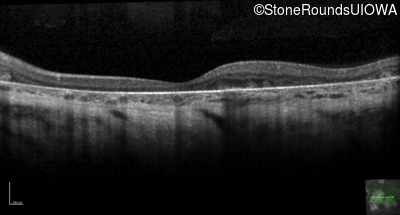

Age at visit: 31 years

This 31 year old woman had subtle macular abnormalities discovered incidentally earlier that year. Her medical history at the time was unremarkable except for gestational diabetes during her most recent pregnancy. Five years later she was diagnosed with type 2 diabetes managed with oral medication. Two years later she developed sufficient hearing loss that hearing aids were required. Her acuity remained 20/20 OU at that time.